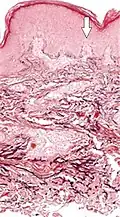

| Actinic elastosis (most common, also called solar elastosis) |

Elastin replacing collagen fibers of the papillary dermis and reticular dermis |

|